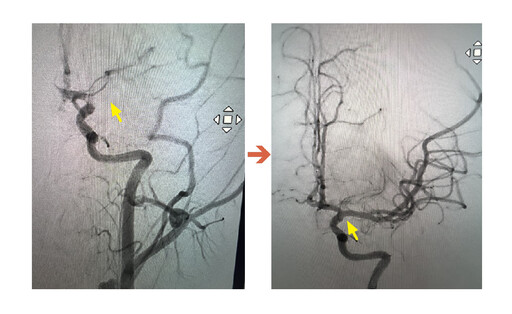

圖:經團隊搶救後,原先受阻的血管(左)已經恢復正常(右)/聯新國際醫院提供

影像檢查結果出爐後,神經內科李振華醫師迅速判讀,確定為左側中大腦動脈栓塞造成缺血性腦中風。在與家屬充分溝通後,影像醫學科主任暨取栓醫師郭葉璘隨即與取栓團隊進行急性腦中風顱內動脈血栓移除(Intra-arterialthrombectomy, IAT),並從腹股溝導引導管至左側中大腦動脈阻塞處,採用強力抽吸方式清除血栓。手術從開始到打通血管僅約10分鐘,成功取出4個血栓,最大達1.1公分,術後患者血流恢復暢通。